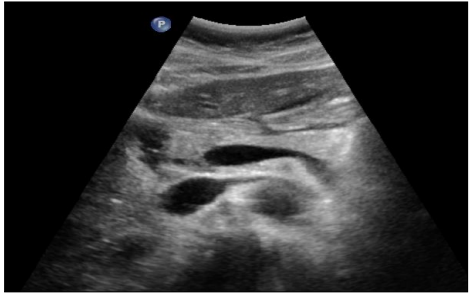

Foie : lésions focales

DANSE E. - UCL

Digestif MASTER 1 Foie

Foie : maladie chronique

MASTER 1